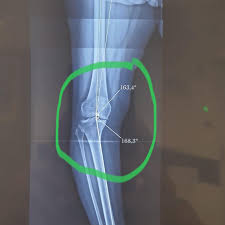

O Sistema Convencional De Placa E Parafusos Na Osteotomia Tibial Alta Em Cunha De Abertura Medial E Suficientemente Estavel Um Estudo Retrospectivo Sciencedirect

Revista Brasileira De Ortopedia O Sistema Convencional De Placa E Parafusos Na Osteotomia Tibial Alta Em Cunha De Abertura Medial E Suficientemente Estavel Um Estudo Retrospectivo